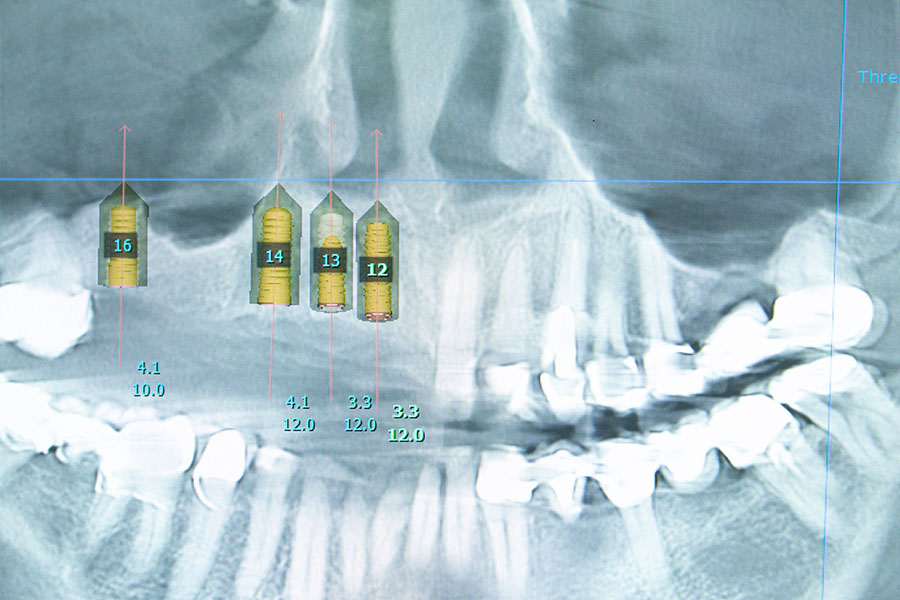

Navigierte Implantation

Die computergestützte 3D-Implantatplanung unter Verwendung von präzisen, individuellen Bohrschablonen ermöglicht dem Operateur den chirurgischen Eingriff genau und sicher zu steuern.

Im Vorfeld werden mit moderner Röntgentechnik (DVT) hochauflösende Bilder von Zähnen und Kieferknochen angefertigt. Durch eine spezielle Software wird anschließend die dreidimensionale Darstellung des Knochens und die Beurteilung der Knochenqualität des Kiefers ermöglicht. Zusätzlich zeigen die Röntgenbilder den Verlauf von Nerven und Blutgefäßen im Operationsgebiet. Die Größe, Lage und Ausdehnung der Kieferhöhlen sowie individuelle anatomische Besonderheiten werden bis ins kleinste Detail dargestellt.

Diese exakte Diagnostik im Vorfeld erlaubt die genaue Planung der zu setzenden Implantate. Aus den Datensätzen angefertigte Bohrschablonen erlauben in Folge die navigierte Implantation, bei der die Bohrtiefe und die Bohrrichtung vorgegeben sind.

Vorteile der 3D Planung:

• Mehr Sicherheit bei komplizierten Kieferverhältnissen, geringem Knochenangebot oder sehr engen Platzverhältnissen im Kiefer.

• Möglichkeit der minimalinvasiven Operation mittels Bohrschablonen, dadurch geringere Blutung und Schwellung.

• Digitaler Workflow: Digitale Datensätze ermöglichen dem Zahnarzt die nachfolgenden Konstruktionen passgenau anzufertigen

• Der Zahnersatz kann nach der Implantation schneller eingegliedert werden, da der Zahnersatz bzw. ein Provisorium bereits vorab geplant und vorbereitet werden kann.

Die Notwendigkeit des Einsatzes der navigierten Implantation hängt von der individuellen Patientensituation ab, aber auch von der Erfahrung des Operateurs.